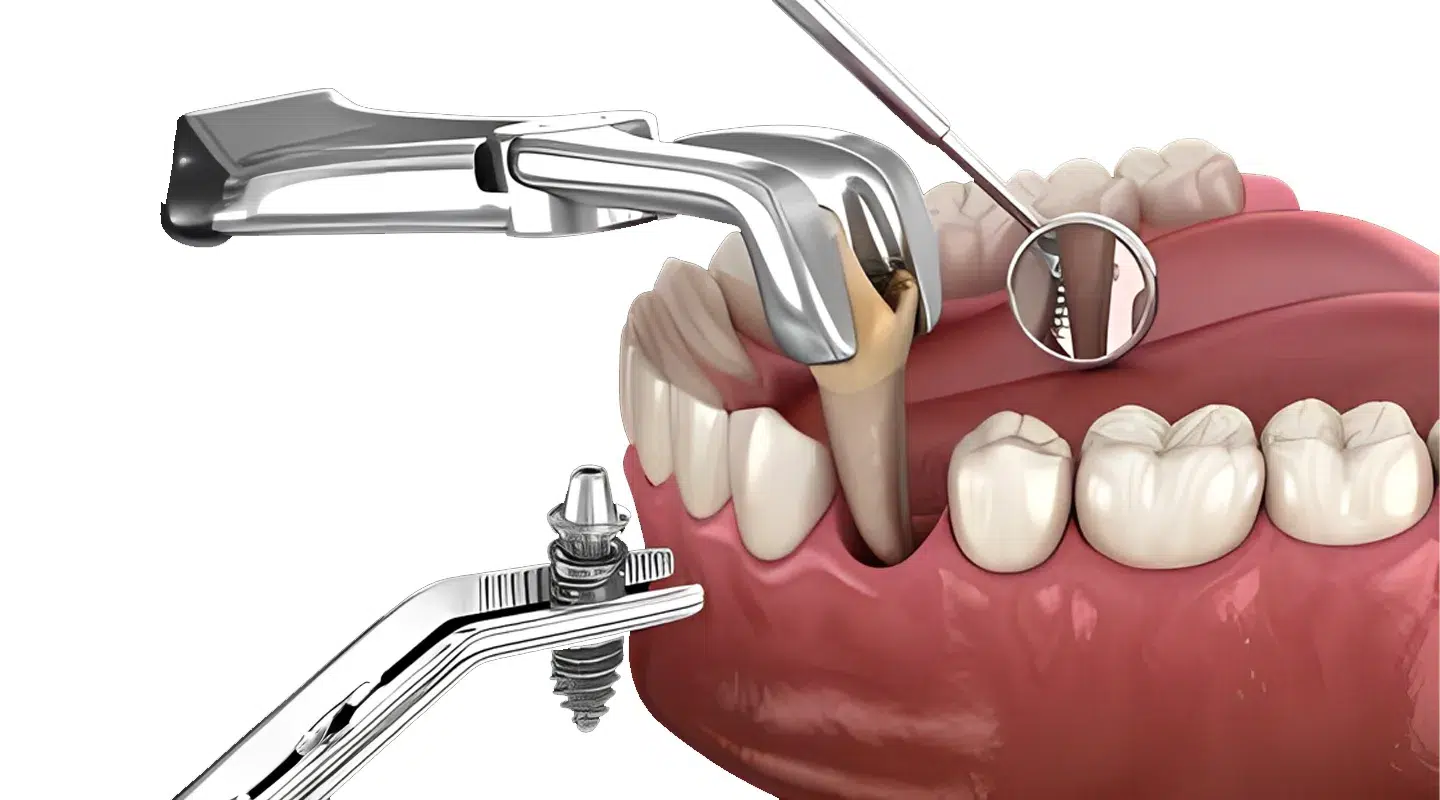

عملية زراعة الأسنان

- في يوم الجراحة، يتم خلع أسنانك وإعادة فحص العظام المحيطة بموقعها. إذا بدا أن العظام غير كافية، فيمكن إضافة الطعوم العظمية خلال هذه المرحلة.

- يتم وضع برغي من التيتانيوم مباشرة بعد إزالة الأسنان وإعداد العظام.